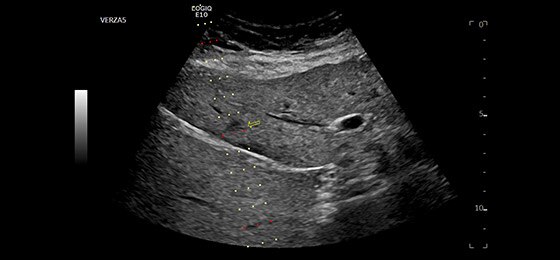

Liver Biopsy with five-angle Verza** needle guide